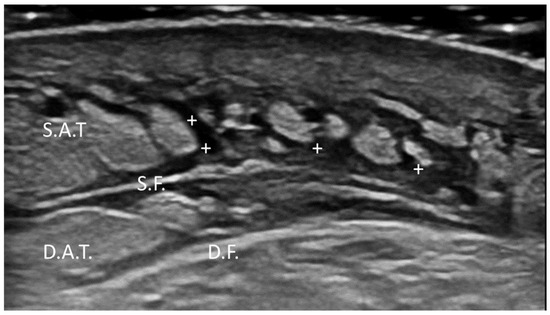

Background/Objectives: Mucoepidermoid carcinoma (MEC) is the most common malignant tumor of the minor salivary glands, often affecting the hard palate. Preoperative diagnosis and surgical planning are challenging due to anatomical complexity and limi...